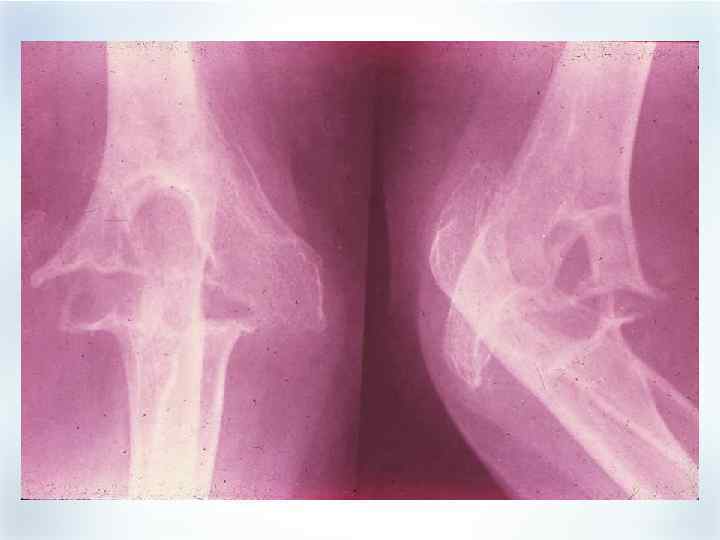

Рентгенологические проявления § § § Ранняя стадия § Припухлость мягкий тканей Средняя стадия § Околосуставной остеопороз § Сужение межсуставных щелей § Костные эрозии Поздняя стадия § Множественные эрозии § Деформации § Остеолиз § Анкилоз Bower AC. In: Klippel JH, Dieppe PA, eds. Rheumatology. Vol 1. 2 nd ed. Philadelphia, PA: WB Saunders; 1998; 5: 5. 1– 5. 8. Resnick D et al. In: Kelley WN et al, eds. Textbook of Rheumatology. 5 th ed. Philadelphia, PA: WB Saunders; 1997: 626– 685.

Рентгенологические проявления § § § Ранняя стадия § Припухлость мягкий тканей Средняя стадия § Околосуставной остеопороз § Сужение межсуставных щелей § Костные эрозии Поздняя стадия § Множественные эрозии § Деформации § Остеолиз § Анкилоз Bower AC. In: Klippel JH, Dieppe PA, eds. Rheumatology. Vol 1. 2 nd ed. Philadelphia, PA: WB Saunders; 1998; 5: 5. 1– 5. 8. Resnick D et al. In: Kelley WN et al, eds. Textbook of Rheumatology. 5 th ed. Philadelphia, PA: WB Saunders; 1997: 626– 685.

Стадии РА По Штейнброкеру (Steinbroker): • практически норма I стадия • околосуставной остеопороз • сужение суставной щели и/или единичные II стадия эрозии ( 10) • околосуставной остеопороз • сужение суставной щели множественные эрозии III стадия (>10) и/или остеолиз (хотя бы 1 области) • + анкилоз (хотя бы 1 области) IV стадия

Стадии РА По Штейнброкеру (Steinbroker): • практически норма I стадия • околосуставной остеопороз • сужение суставной щели и/или единичные II стадия эрозии ( 10) • околосуставной остеопороз • сужение суставной щели множественные эрозии III стадия (>10) и/или остеолиз (хотя бы 1 области) • + анкилоз (хотя бы 1 области) IV стадия

Прогрессирование деструкции за 7 лет болезни

Прогрессирование деструкции за 7 лет болезни